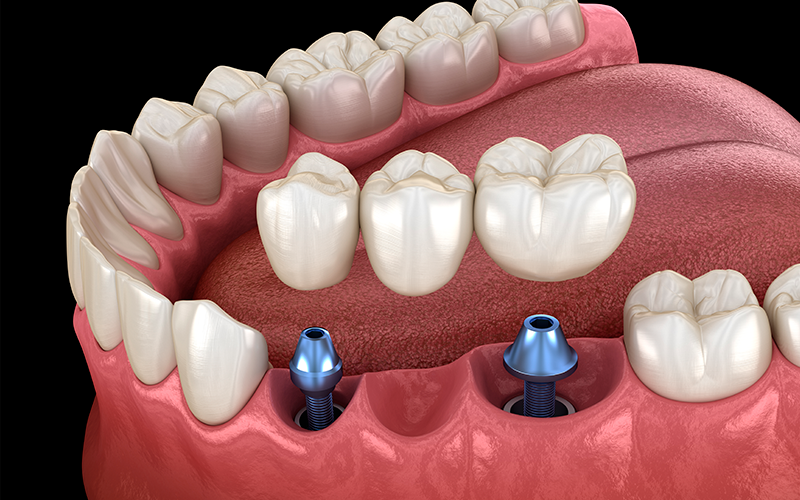

¿Qué es un implante dental?

Un implante dental es una pequeña pieza de titanio que se coloca en el hueso de la mandíbula para reemplazar una pieza dental perdida. Imagina que tienes un diente que ya no puedes salvar; con un implante, podemos poner uno nuevo que se ve y funciona como el original, devolviéndote la capacidad de masticar bien, sonreír con confianza y hablar sin temor.